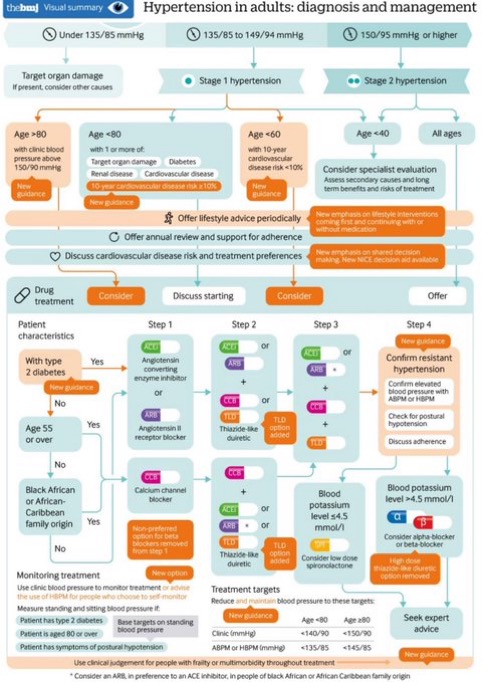

📋Diagnóstico y manejo de la hipertensión: resumen de las guías del NICE del Reino Unido 👇 #cardiologia #HTA #CardioEd